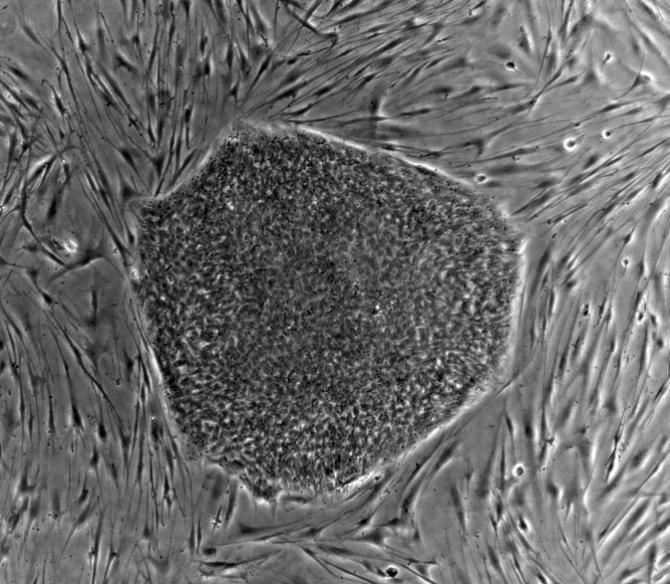

人類胚胎干細胞(hES)

干細胞是一種未被賦予特定功能的細胞,即它們的基因表達模式還尚未被固化。干細胞既能幾乎無限制的進行細胞分裂,生成新的干細胞,也可以在特定的環境下分化成特殊職能化的細胞,例如神經細胞、血液細胞。

干細胞一般有兩種來源,一種少部分存在于成年個體的組織器官中,例如:我們如果去少量獻血,并不會馬上死掉,骨髓中的造血干細胞會馬上動員起來,分化為血液細胞,這樣你又可以活蹦亂跳了。而另外一種,功能更為強大,從發育早期胚胎分離得到的胚胎干細胞,它與成體干細胞不同,具有更高的多能性,可以轉變為人體的任何的細胞、組織甚至器官,是一種真正萬能細胞。